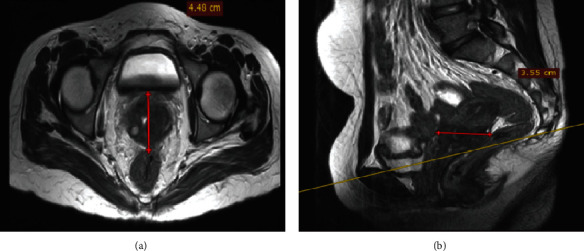

简介原发性对角线外生殖细胞瘤(EGCTs)是一种非常罕见的临床疾病,最常见于男性。在女性中,胎盘、骨盆、子宫、大脑和纵隔是最常见的生殖细胞瘤部位,其组织学主要表现为非生殖细胞瘤。在本报告中,我们介绍了一例年轻女性患者的原发性宫颈胚胎发育不良瘤。病例报告。一名 18 岁的无生育能力女性因 12 个月的阴道出血和分泌物病史前来就诊。血常规检查和血清肿瘤标志物水平均在正常范围内。胸部 X 光检查正常。高分辨率盆腔磁共振成像显示,宫颈阴道肿块轮廓清晰,大小为 8 × 6 × 5 厘米,向阴道口扩展,呈轻度均质对比增强。患者在麻醉状态下经阴道进行了切口活检,组织学检查结果与畸形精原细胞瘤一致。再次复查盆腔磁共振成像显示,肿块缩小了 70% 以上。患者接受了 4 个周期的博来霉素、依托泊苷和顺铂化疗。在获得部分反应后,又进行了盆腔外放射治疗。放疗 3 个月后,对比腹盆腔 CT 扫描显示宫颈阴道肿块复发,并向盆腔侧壁扩展。患者因生殖细胞瘤复发开始接受伊佛酰胺、紫杉醇和顺铂(ITP)二线化疗,但后来死于肾积水、慢性贫血和败血症:结论:子宫颈是原发性生精细胞畸形瘤的一个非常不寻常的部位,其临床病程可能非常凶险。要确诊该病,尤其是对宫颈病变的年轻患者,必须高度怀疑并进行全面检查。

Introduction: Primary extragonadal germ cell tumors (EGCTs) are a very rare clinical encounter most commonly reported in males. Among females, the placenta, pelvis, uterus, brain, and mediastinum are the most common extragonadal sites and predominantly display nondysgerminoma histology. In this report, we present a case of a primary cervical dysgerminoma in a young female patient. Case Report. An 18-year-old nulligravid woman presented with a 12-month history of vaginal bleeding and discharge. Routine blood tests and serum levels of tumor markers were within normal limits. The chest X-ray was normal. A high-resolution pelvic MRI showed a well-defined lobulated cervicovaginal mass measuring 8 × 6 × 5 cm expanding into the vaginal canal with mild homogenous contrast enhancement. An incisional biopsy was performed vaginally under anesthesia, and histologic findings were consistent with dysgerminoma. A repeat follow-up pelvic MRI was done and showed a reduction in the size of the mass by more than 70%. The patient was treated with 4 cycles of bleomycin, etoposide, and cisplatin chemotherapy. Additional external pelvic beam radiation treatment was administered for a partial response. After 3 months of radiotherapy, a contrast abdominopelvic CT scan showed a recurrent cervicovaginal mass with extension to the pelvic sidewalls. The patient was initiated with ifosfamide, paclitaxel, and cisplatin (ITP) as second-line chemotherapy for a recurrent germ cell tumor but later died from hydronephrosis, chronic anemia, and sepsis.